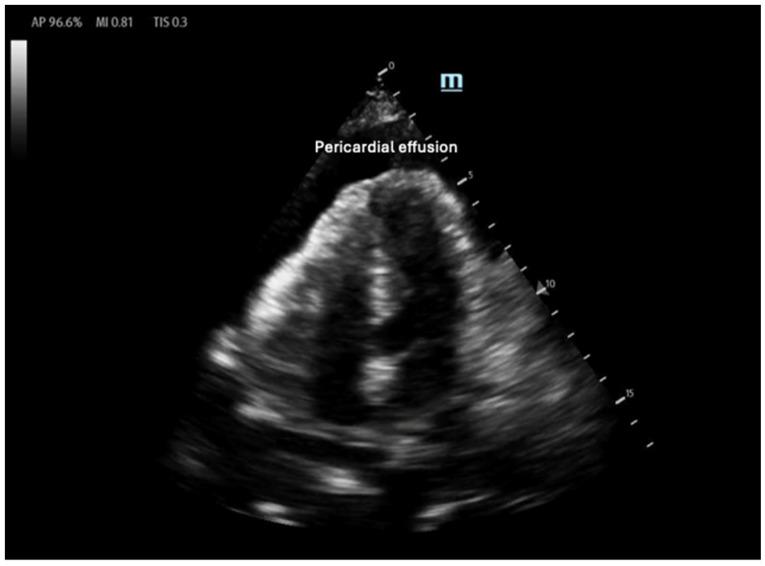

床旁超声在血流动力学评估中的应用

Point-of-Care Ultrasound Use in Hemodynamic Assessment.

Hemodynamic assessment is critical in emergency and critical care for preventing, diagnosing, and managing shock states that significantly affect patient outcomes. Point-of-care ultrasound (POCUS) has become an invaluable, non-invasive, real-time, and reproducible tool for bedside decision-making. Advancements such as Doppler imaging, advanced critical care ultrasonography, and transesophageal echocardiography (TEE) have expanded its utility, enabling rapid and repeatable evaluations, especially in complex mixed shock presentations. This review explores the role of POCUS in hemodynamic monitoring, emphasizing its ability to assess cardiac output, filling pressures, and vascular congestion, facilitating shock classification and guiding fluid management. We highlight an extensive array of POCUS techniques for evaluating right and left cardiac function and review existing literature on their advantages, limitations, and appropriate clinical applications. Beyond assessing volume status, this review discusses the role of POCUS in predicting fluid responsiveness and supporting more individualized, precise management strategies. Ultimately, while POCUS is a powerful tool for rapid, comprehensive hemodynamic assessment in acute settings, its limitations must be acknowledged and thoughtfully integrated into clinical decision-making.

血流动力学评估在急诊和重症监护中对于预防、诊断和处理显著影响患者预后的休克状态至关重要。床旁即时超声检查(POCUS)已成为一种用于床边决策的宝贵、非侵入性、实时且可重复的工具。诸如多普勒成像、高级重症监护超声检查和经食管超声心动图(TEE)等技术进步扩展了其用途,能够进行快速且可重复的评估,尤其是在复杂的混合性休克表现中。本综述探讨了POCUS在血流动力学监测中的作用,强调其评估心输出量、充盈压和血管充血情况的能力,有助于休克分类并指导液体管理。我们重点介绍了一系列用于评估左右心功能的POCUS技术,并回顾了关于它们的优势、局限性及适当临床应用的现有文献。除了评估容量状态外,本综述还讨论了POCUS在预测液体反应性以及支持更个体化、精确的管理策略方面的作用。最终,虽然POCUS是急性情况下进行快速、全面血流动力学评估的有力工具,但必须认识到其局限性并谨慎地将其纳入临床决策。